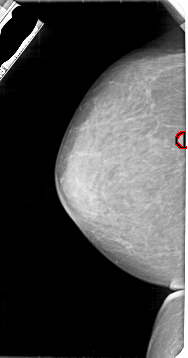

A_1947_1.RIGHT_CC

RIGHT_MLO LINES 5491 PIXELS_PER_LINE 2761 BITS_PER_PIXEL 12 RESOLUTION 43.5 NON_OVERLAY

FILE: A_1947_1.LEFT_CC.OVERLAY

TOTAL_ABNORMALITIES 1

ABNORMALITY 1

LESION_TYPE MASS SHAPE ROUND MARGINS CIRCUMSCRIBED

ASSESSMENT 3

SUBTLETY 4

PATHOLOGY BENIGN

TOTAL_OUTLINES 1

BOUNDARY